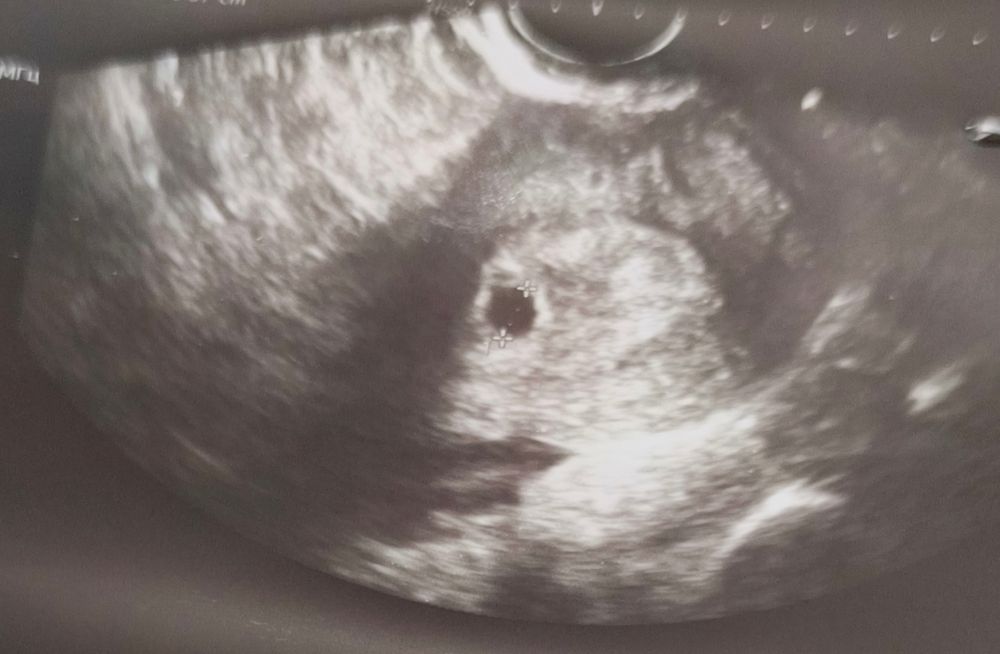

С утра очень сильно перемкнуло, что у меня внематочная 😅 тянуло где-то справа. Записалась в ближайшую клинику на УЗИ, сейчас шла домой из клиники и хохотала - мало того, что ПЯ в полости матки, так ещё и жёлтое тело в левом яичнике, а справа видимо ощущались связки))

На УЗИ пока только ПЯ, но всё сходится с моими расчетами, по ХГЧ должно примерно так и быть. И размером оно больше, чем в прошлую неудачную беременность на 7+1. Через неделю посмотрю на хорошем аппарате динамику, а пока можно выдохнуть. ПЯ в матке - уже полдела))